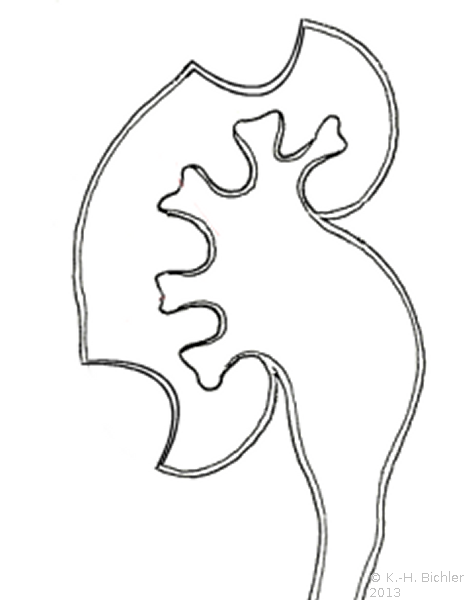

Die Refluxnephropathie ist von einer fortschreitenden Destruktion des Nierenparenchyms geprägt (Abbildung 7). Die pathologischen Veränderungen sind dabei abhängig vom Grad des Refluxes und oder der bakteriellen Infektion.

Die Nieren sind klein und haben ein Gewicht von ca. 40g. Die Nierenoberfläche ist diffus-höckrig. Refluxnarben finden sich an den Polen und der Mitte des Organs. Auf der Schnittfläche zeigt sich das Parenchym reduziert, z.T. mit abgeflachten Papillen und Bildung von Exkavationen bzw. Rezessi (Abbildung 7,8,9)